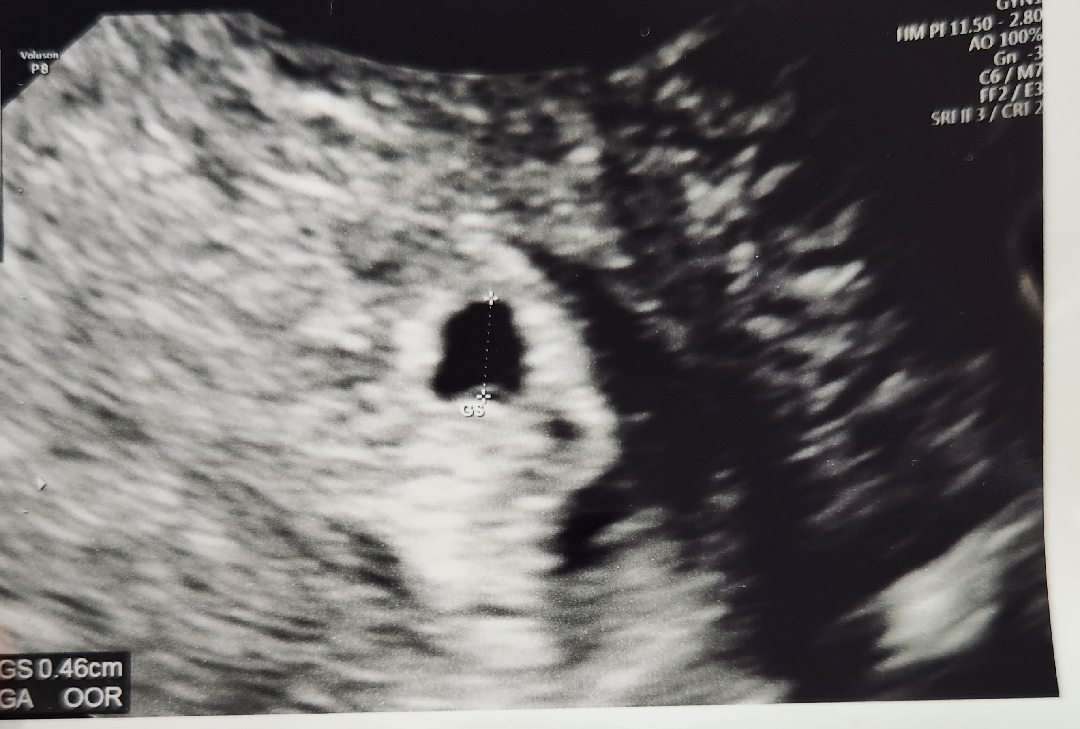

5주0일 둘째여도 설레이네용ㅎ

예정일은 10월19일에요ㅎ 첫찌가 10월15일생인데.. 된다면 15일 유도분만해서 생일맞추고싶네용ㅎ 자궁근종2cm가 보인다는데 좀 걱정되는데 괜찮겠죠ㅠ